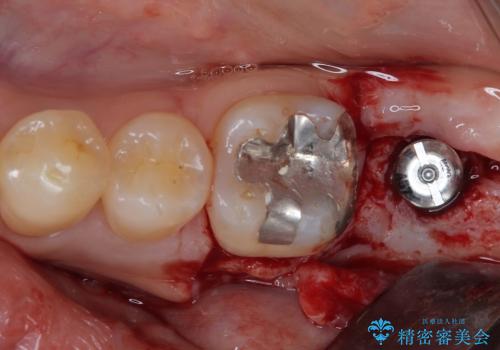

左下の奥歯は状態が非常に悪く、保存は困難と判断されたため、インプラントによる補綴治療が必要でした。

上顎左右の歯をアンカースクリューを用いた部分矯正により位置を修正し、オールセラミッククラウンにて補綴治療を行うこととしました。